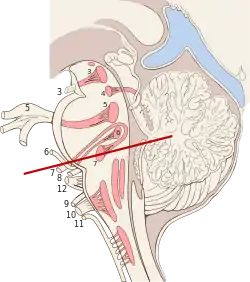

Primary terminal nuclei of the afferent (sensory) cranial nerves schematically represented; lateral view. Brain stem sagittal section

Brain stem sagittal section